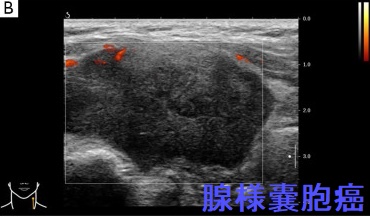

甲状腺浸潤して甲状腺腫瘍のように見えた腺様嚢胞癌の報告があります[Gland Surg. 2024 Apr 29;13(4):571-577.]。